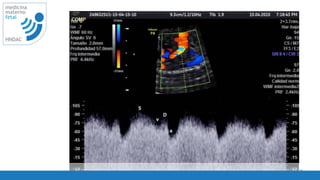

utilidad

• Diagnostico de insuficiencia placentaria

• RCIU

• Embarazo multiple